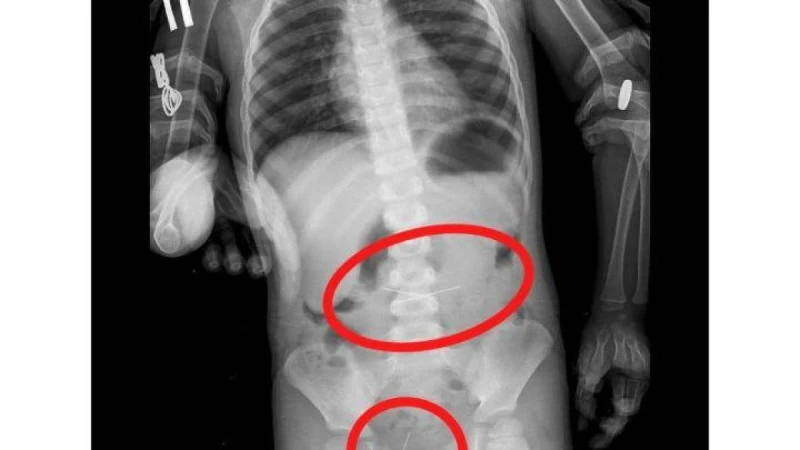

Баланың іш қуысының шолу рентгенографиясында дәрігерлер жүгіргішті және асқазанның проекциясында екі тігін инесін анықтады. FGDS процедурасы кезінде олардың біреуі алынып тасталды.

Бала бақылауда болды. Көп ұзамай дәрігерлер іш қуысының R-граммында жамбас проекциясында төртінші инені тапты. Колоноскопия жасалды және сигма тәрізді ішектен соңғы ине алынып тасталды. Қазіргі уақытта баланың жағдайы бірқалыпты.